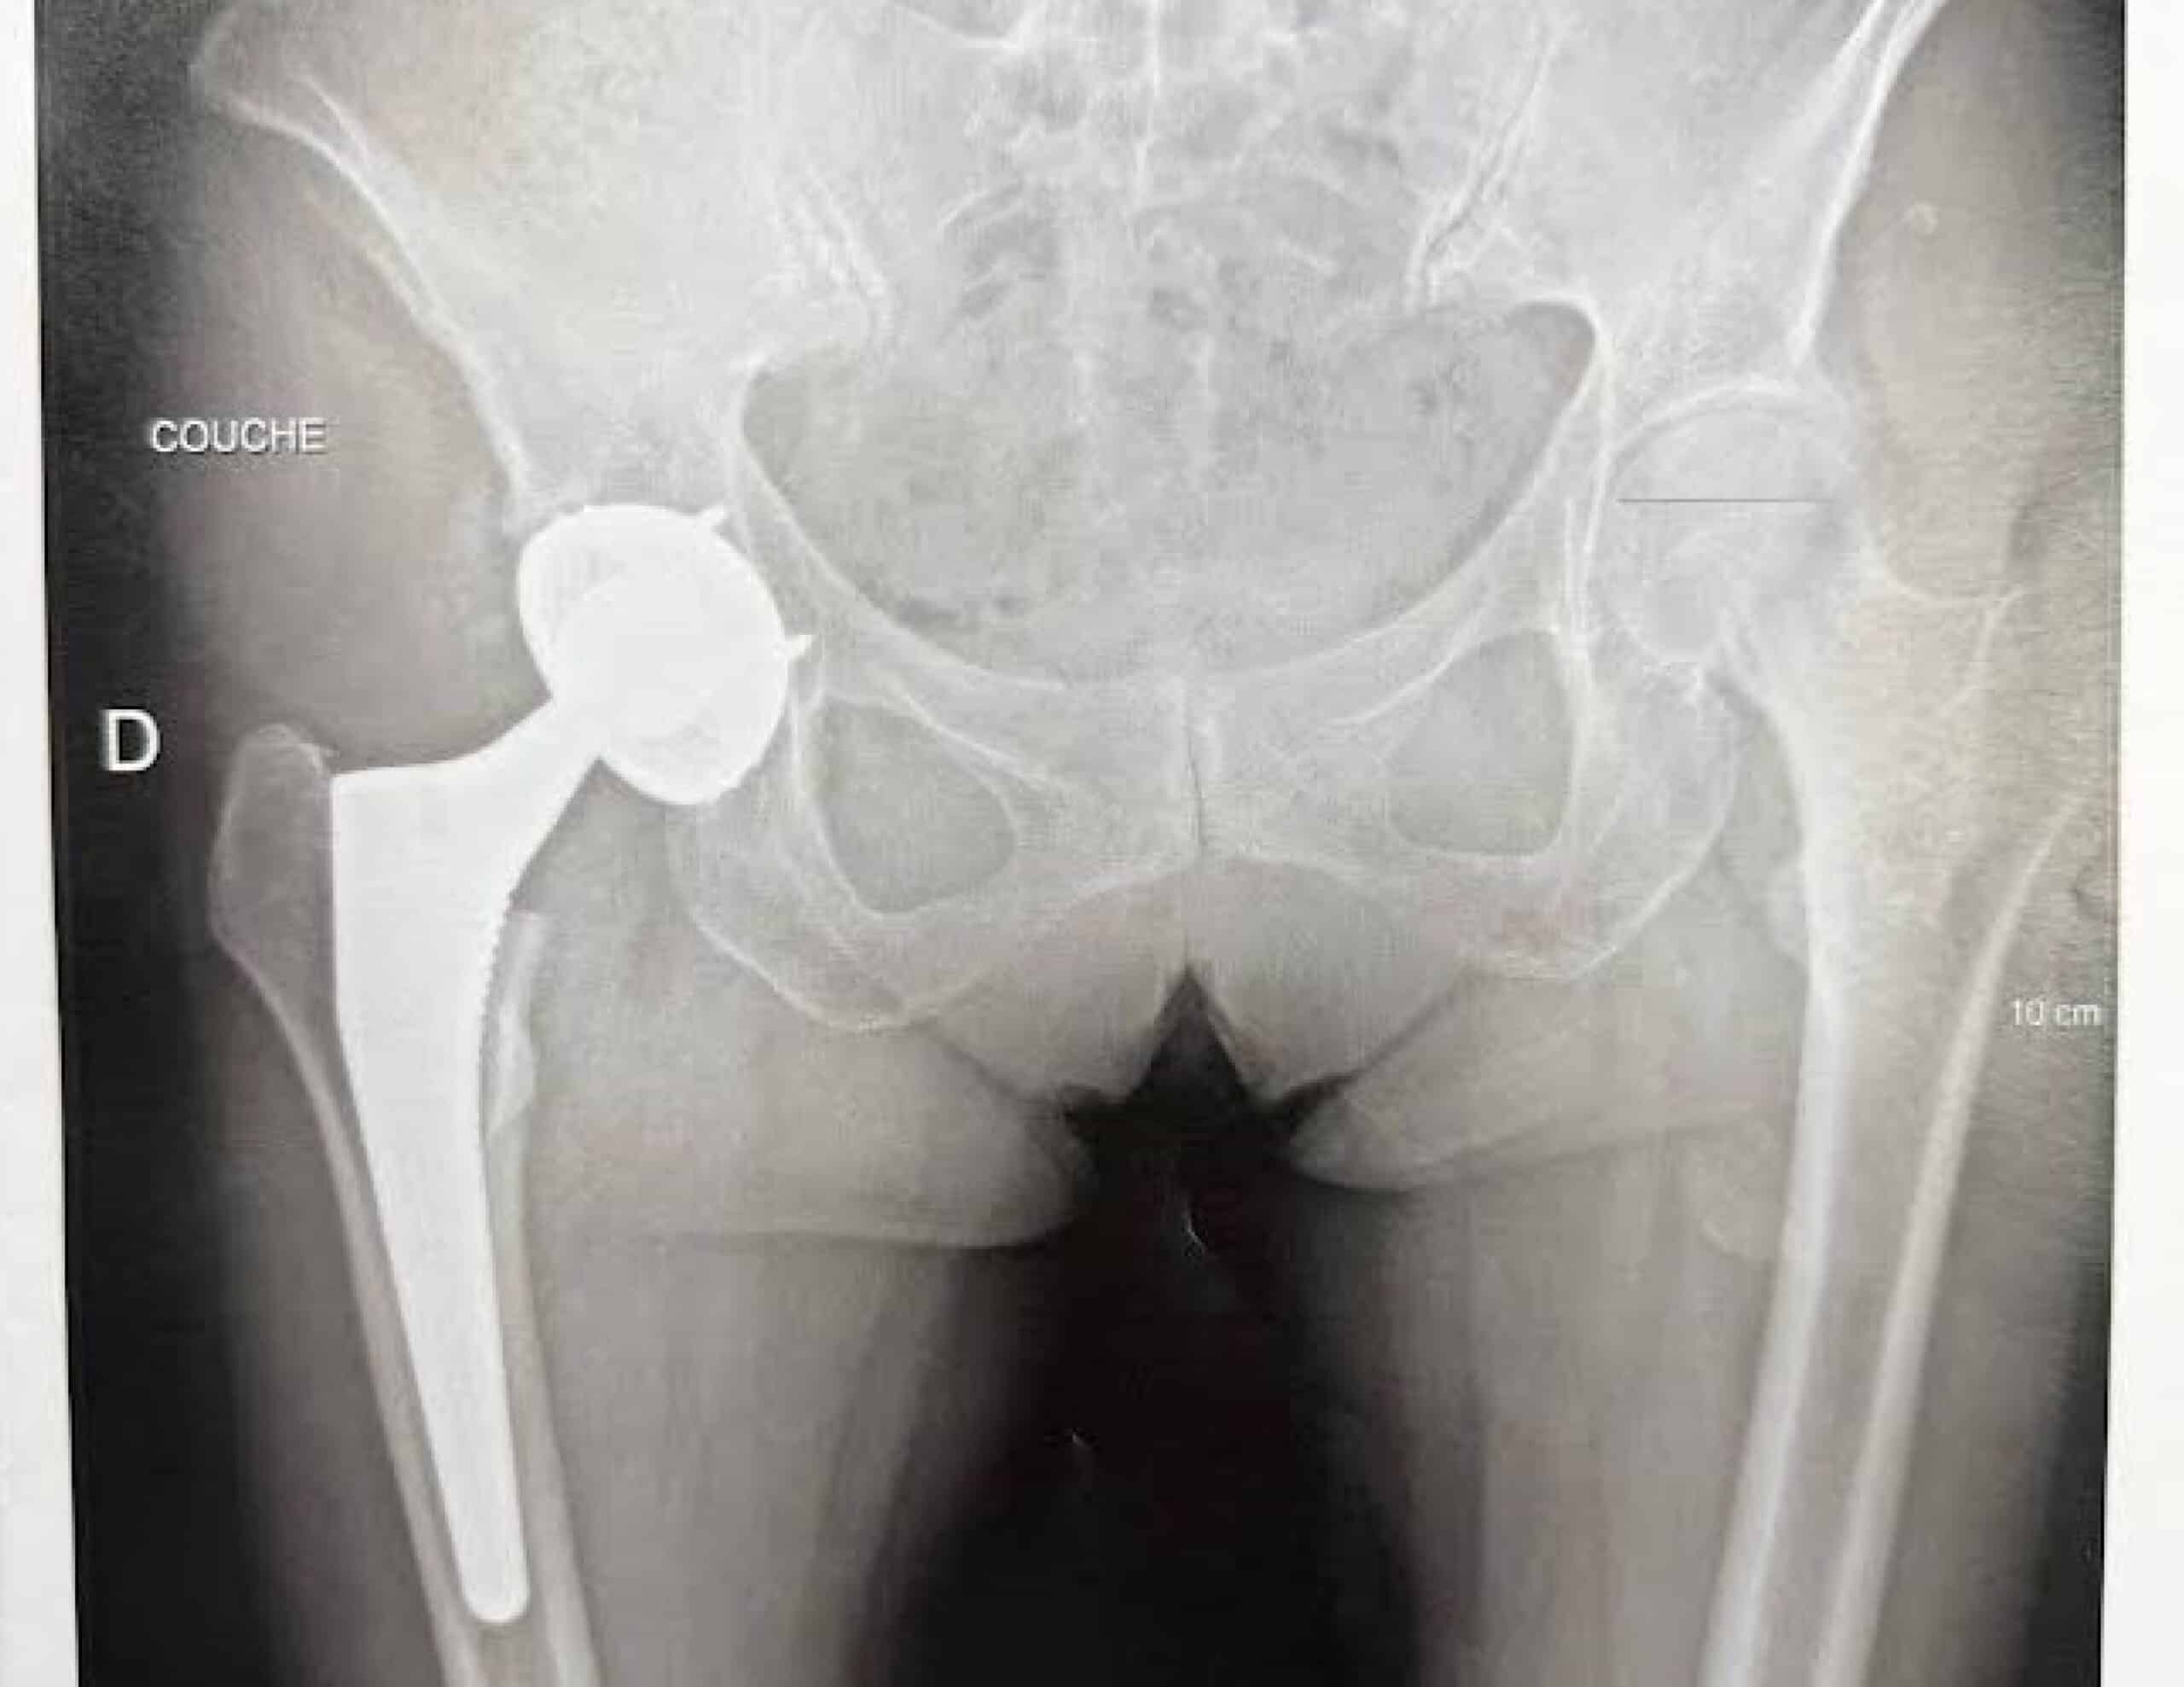

Radiological assessment is essential to quantify the leg length difference. Standing anteroposterior pelvic radiographs, both pre- and postoperatively, should be analyzed.

An EOS full-body standing scan (spine and lower limbs) can measure bone segment lengths and assess the lumbopelvic-femoral balance.

However, the reference examination remains 3D CT imaging, which allows precise geometric analysis.

Unfortunately, many patients did not undergo preoperative CT imaging, making it difficult to obtain accurate measurements of native joint geometry.

When a preoperative CT scan is available, a postoperative scan can perfectly reveal the geometric changes induced by surgery. If not, a bilateral CT scan can compare the operated and non-operated hips to identify asymmetries.

3D CT analysis to identify the cause of discrepancy

3D CT analysis is critical, as the sensation of leg length inequality often combines three interrelated mechanical issues :

• Excessive vertical lengthening (cranio-caudal axis)

• Uncontrolled variation of the medio-lateral offset

• Uncontrolled change in femoral anteversion (axial plane)

Through detailed 3D analysis, it becomes possible to identify cup malposition, femoral stem malalignment, or inaccurate adjustment of soft-tissue tension related to the choice of prosthetic head.